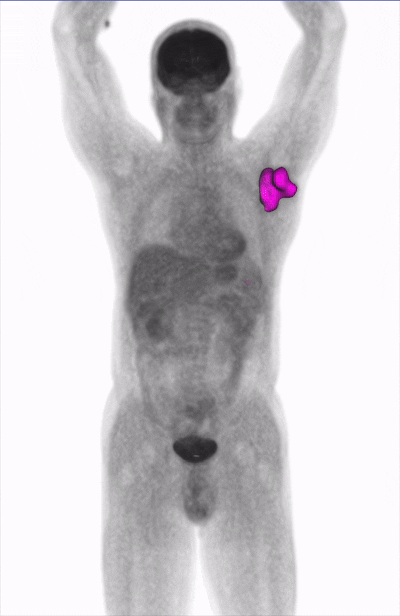

Штучний інтелект, розроблений російськими програмістами, швидко визначає внутрішні патології відповідно до зображень КТ, ПЕТ та МРТ. Діагностична точність 98,8%.

Так, це: проект “Blumind ai«Це дійсно діагностує краще, ніж лікар – штучний інтелект, розроблений російськими програмістами, визначає внутрішні патології швидше. Спеціалізований ШІ робить це із зображень КТ, ПЕТ та МРТ. Точність діагностики становить 98,8%.

Зазвичай лікар -лікар призначає напрямок на КТ, ПЕТ або МРТ. Пацієнт приходить до рентгенівської шафи і фотографує. Ці скани вивчаються “Blumind AI”. Він здатний дати опис за три хвилини, що набагато швидше, ніж людина. AI може заощадити до 200 годин на одному дослідженні, кажуть розробники Bluemind AI. Більше того, це може створити 3D -візуалізацію внутрішніх органів людини і чітко показати, наприклад, пухлину.